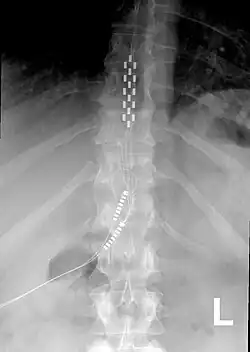

Anterior view X-ray of a spinal cord stimulator (SCS) implanted in the thoracic spine

A spinal cord stimulator (SCS) or dorsal column stimulator (DCS) is a type of implantable neuromodulation device (sometimes called a "pain pacemaker") that is used to send electrical signals to select areas of the spinal cord (dorsal columns) for the treatment of certain pain conditions. SCS is a consideration for people who have a pain condition that has not responded to more conservative therapy.[1] There are also spinal cord stimulators under research and development that could enable patients with spinal cord injury to walk again via epidural electrical stimulation (EES).[2][3]